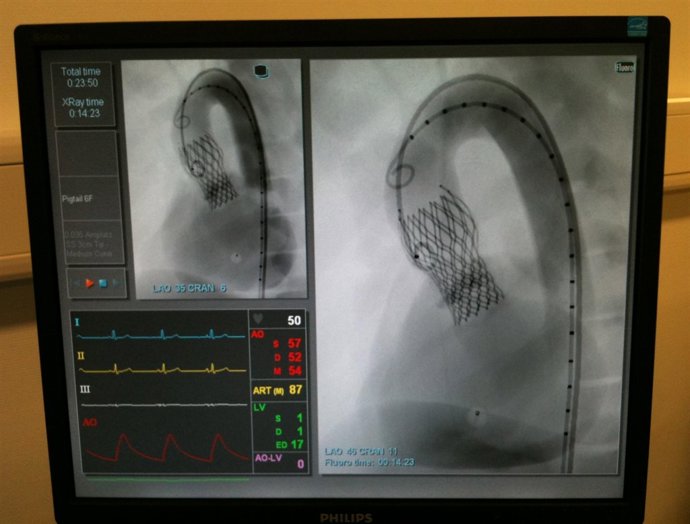

Imagen de la colocación de la válvula

Esta intervención consiste en introducir una válvula plegada a través de una pequeña incisión en la arteria femoral y conducirla con un catéter usando imágenes de radioscopia hasta el anillo valvular aórtico. Una vez allí, la válvula, que es autoexpandible, se despliega sobre la válvula nativa y asume sus funciones para resolver, así, el problema de una estenosis aórtica grave.

Las válvulas aórticas autoexpandibles que se implantaron están fabricadas de pericardio porcino y van sujetas con un stent (una especie de malla) de nitinol (una aleación de níquel).